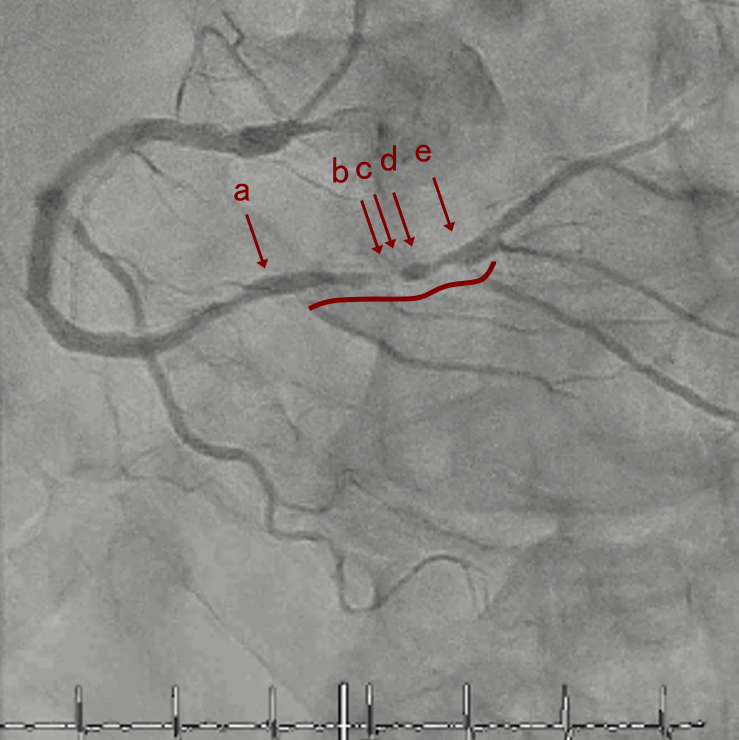

CAG

RCA distalの高度石灰化狭窄病変

PreのIVUSではaの部位のみlipid plaqueを認め削ることでdistal embolismのリスクがあり、そのほかは270度の偏心性石灰化であるがwire biasは良好。

OAS low speedによる引きを赤線の区間行う方針とした。